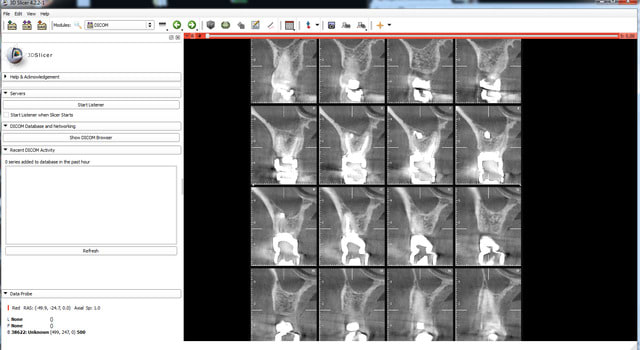

essayes SLICER 4.3

il marche plutôt bien mais nécessite un peu de temps d'adaptation.

tu installes tu lances. Tu cliques sur LOAD data.

tu selectionnes ton dossier. tu cliques sur Import. tu load ton dossier.

Après tu cliques sur le + a coté du nom du patient.

tu sélectionnes le bon fichier Dx dans l'arbre ainsi déroulé.

puis dans la fenêtre inférieur tu cliques "load selection to SLICER"

pour la génération de modèles 3D c'est pas très jojo. faut bosser sur Meslab après et sous 3ds max.